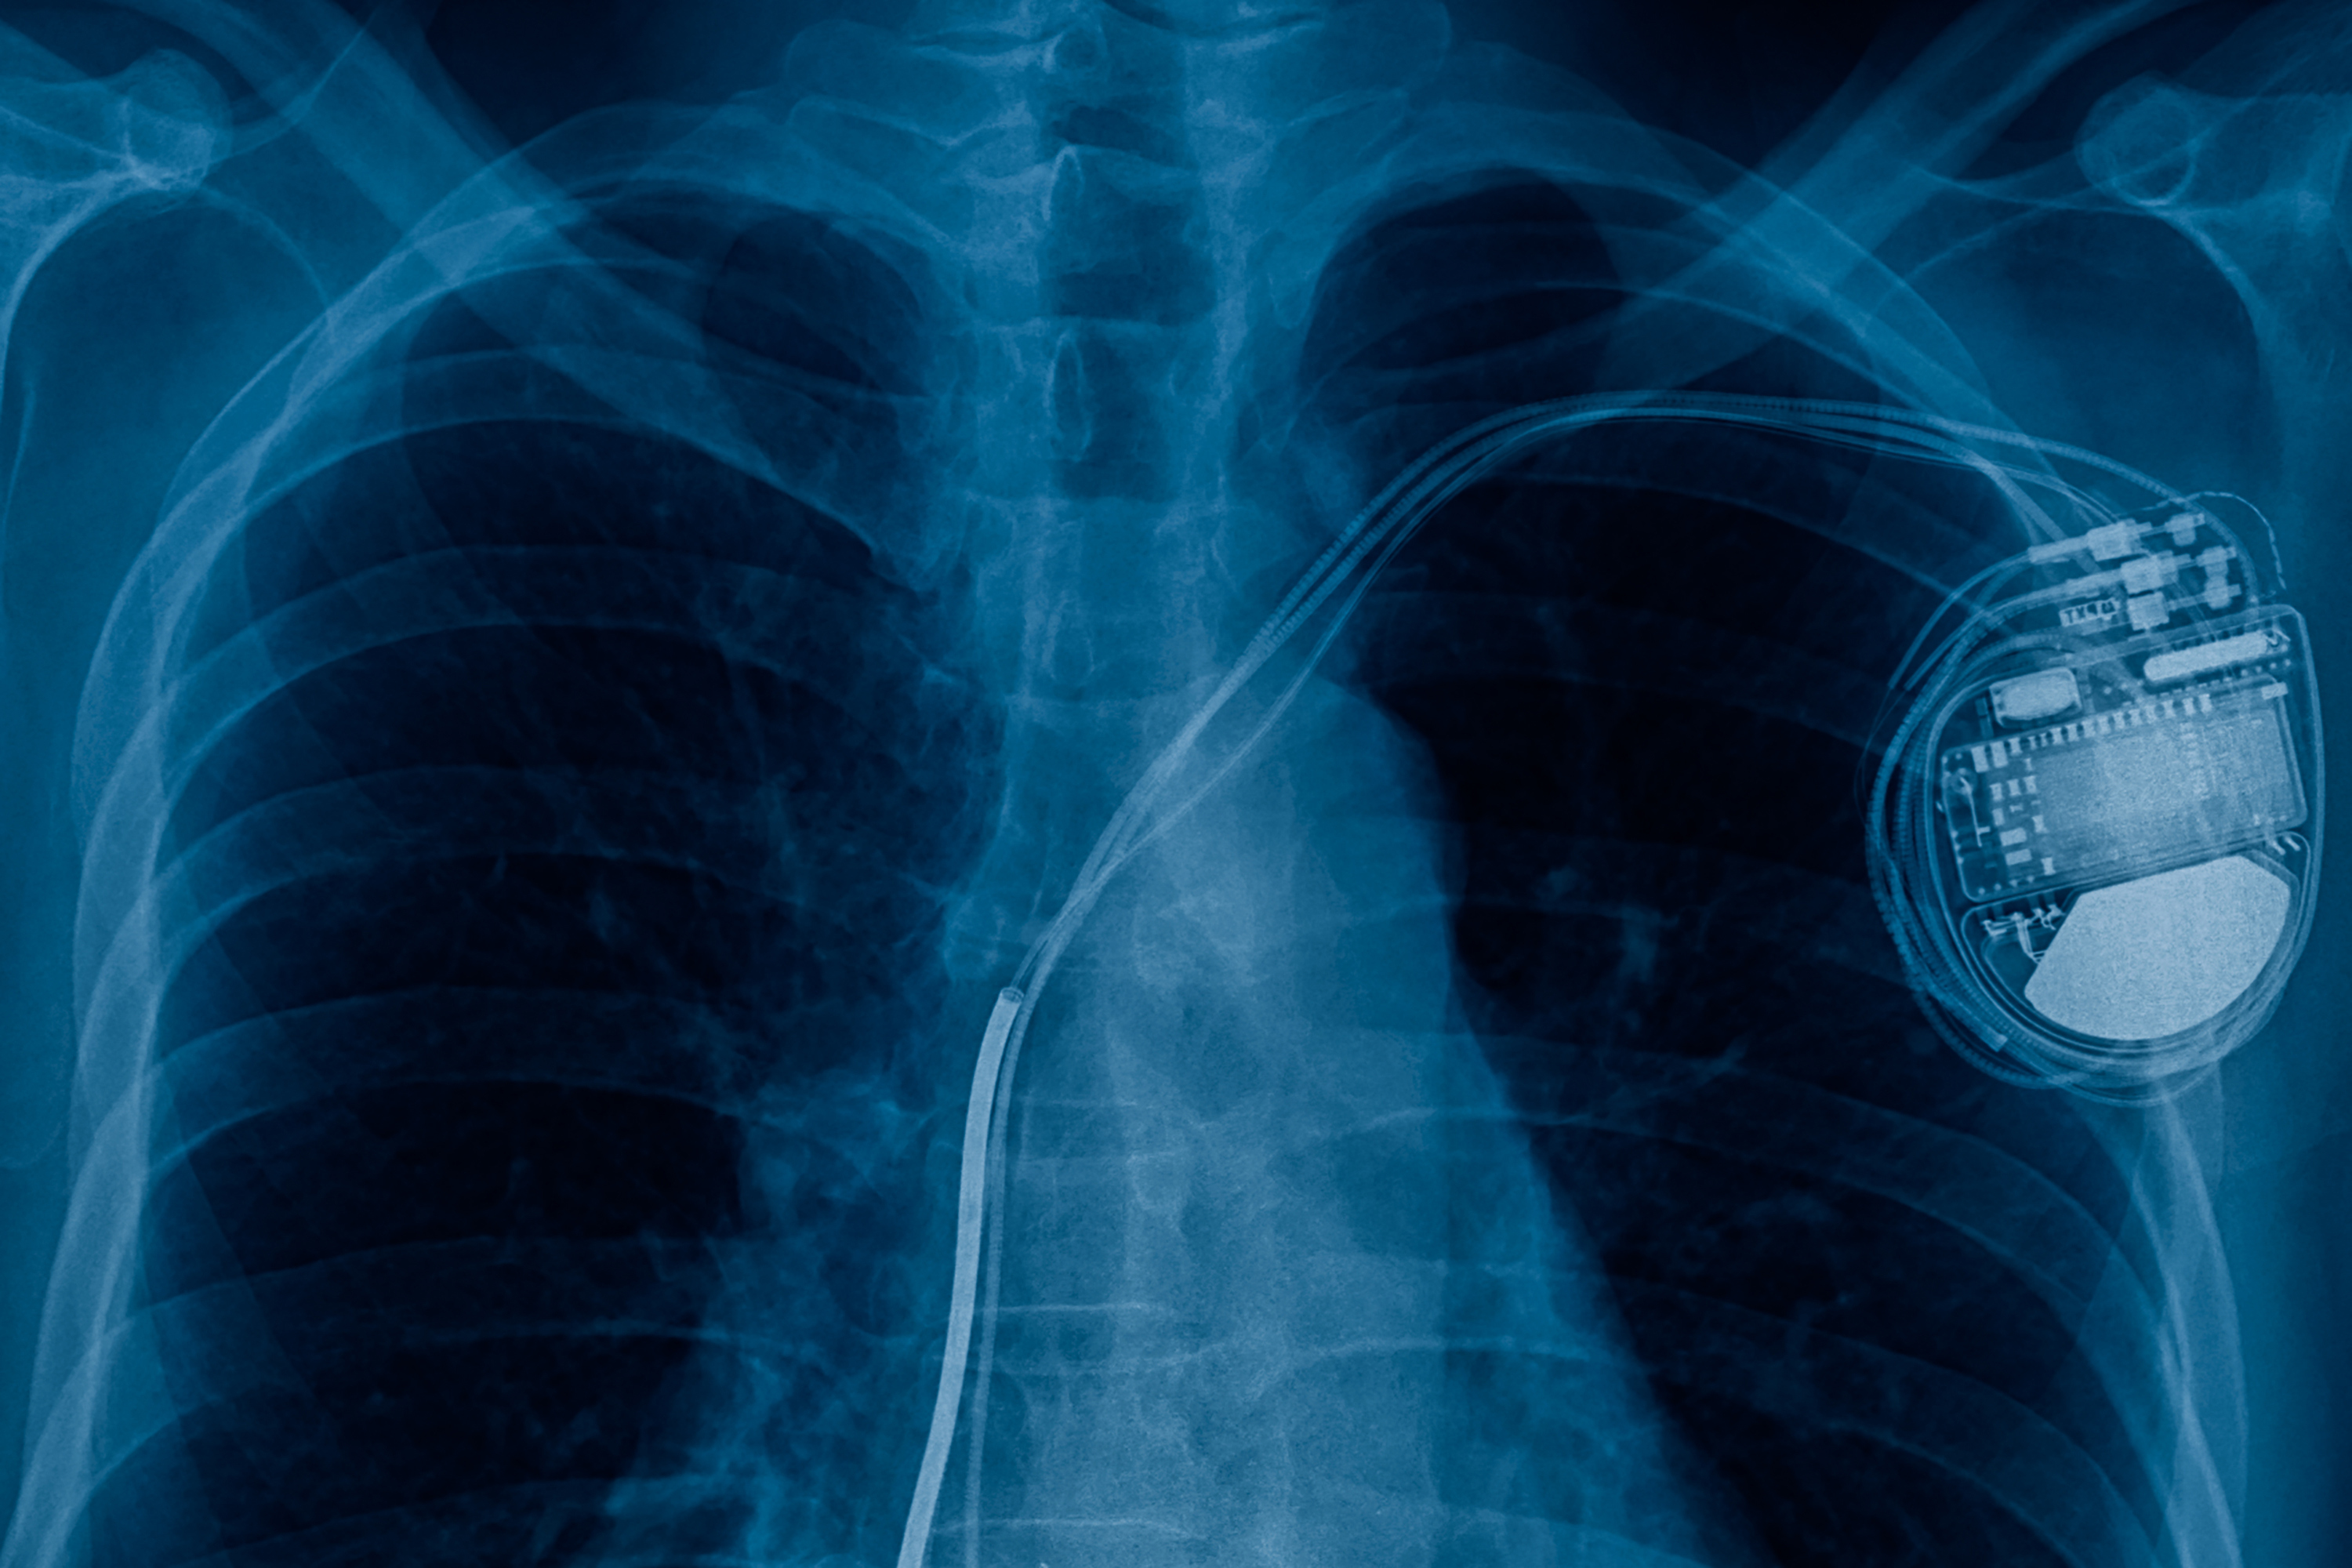

A pacemaker is a small metal, electrical device which is inserted into the chest. It is used to treat arrhythmias (abnormal heart rhythms), for example if the heart beats too slowly, known as bradycardia.

Some pacemakers (biventricular) help the chambers beat in sync and can treat heart failure. Another type of metal cardiac device is an implantable cardioverter defibrillator (ICD), these are used to treat patients who have had, or are at risk of life-threatening arrhythmias.

As MRI scans use strong magnetic fields they can disrupt and damage metal devices such as pacemakers. Historically, having a pacemaker was a clear contraindication to having an MRI scan, however newer devices are MRI compatible, and some research has shown that even older devices are safe.

The strong magnetic fields can heat the metal pacemaker, damaging the heart tissue or modifying the pacemaker's settings. Subsequently in patients with pacemakers or other implantable cardiac devices, MRI scans have been discouraged or prohibited, and alternative, often less effective, imaging techniques are used.